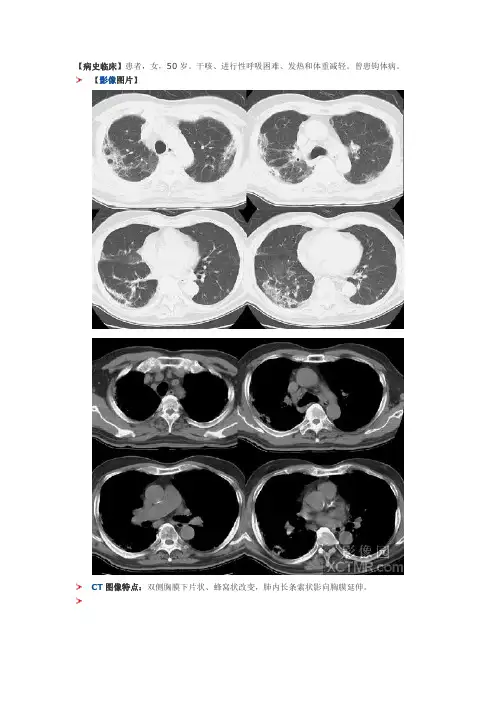

【病史临床】患者,女,50岁。

干咳、进行性呼吸困难、发热和体重减轻。

曾患钩体病。

【影像图片】CT图像特点:双侧胸膜下片状、蜂窝状改变,肺内长条索状影向胸膜延伸。

结果:慢性嗜酸细胞性肺炎点评:本病是寄生虫(钩虫、蛔虫等)和药物(呋喃妥因等)所致的变态反应,为肺部嗜酸粒细胞浸润的一种消耗性疾病。